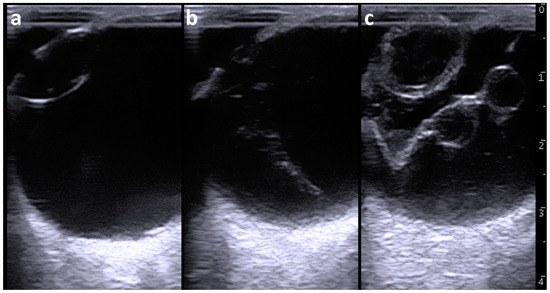

Ocular ultrasonography was carried out using a portable-type ultrasound machine (MyLabOne VET, Esaote Co., Genoa, Italy). Prior to the examination, an ophthalmic local anesthetic (Benoxil ophthalmic solution 0.4%, Santen Pharmaceuticals Co., Ltd., Osaka, Japan) was topically applied for the surface of the cornea. A 10.0 MHz linear probe was applied to the surfaces of the cornea in the horizontal plane (medial to lateral direction) soon after topical use of an ultrasound gel, while the animal was kept in standing position without sedation. Ultrasonography of the left eyeball revealed that the anterior aqueous and vitreous humors were normally anechoic (Figure 2a). The anechoic lens was surrounded by echogenic lines of the anterior and posterior lens capsules. A corn-like echogenic structure appeared between the posterior lens capsule and the deepest scleroretinal rim within the vitreous body when the probe was slightly moved medially from the center (Figure 2b). It was unclear whether the proximal region of this structure had adhered to the posterior lens capsule. The widest proximal region of the corn-like echogenic structure was approximately 1 cm thick. The distal region of this structure adhered to the deepest scleroretinal rim (possibly corresponding to the optic disc) and was thinnest at 2 to 3 mm thickness. A persistent hyaloid artery was suspected based on this ultrasonographic finding.

Figure 2.

Ultrasonographic appearances of the left eyeball (a,b) and right eyeball (c). (a) The lens is anechoic and surrounded by echogenic lines of the anterior and posterior lens capsules within the left eyeball. (b) The corn-like structure is heterogeneously echogenic and present between the posterior lens capsule and the deepest scleroretinal rim within the vitreous body of the left eyeball. (c) A V-shaped membranous structure is present and accompanied by two cystic structures within the vitreous body of the right eyeball. The enlarged lens is heterogeneously anechoic to hypoechoic and is lined by the thickened and irregular anterior and posterior lens capsules. Scale = 10 mm.

Ultrasonography of the right eyeball revealed that the lens was lined by thickened and irregular anterior and posterior lens capsules (Figure 2c). The anterior lens capsule appeared as a heterogeneous and 3 to 4 mm thick structure and was slightly thicker compared with that of the posterior lens capsule (2 to 3 mm thickness). The posterior lens capsule appeared as a heterogeneous echogenic architecture lined by two hyperechoic anterior and posterior lines. The lens was heterogeneously seen with a mixture of anechoic and hypoechoic contents. The vitreous humor was heterogeneously anechoic and included hypoechoic contents. A V-shaped membranous structure could be seen within the vitreous body. The membranous structure was irregular and 1 to 3 mm thick. The tip of the V-shaped structure was located in the area of the optic disc, although it was unclear whether it ended within the optic disc. The two proximal edges of the V-shaped structure ended in the scleroretinal rim near the ciliary body. Two cystic structures were formed alongside each other in the center of one line of the V-shape of the membranous structure. The cystic structures were outlined by irregular and 1 to 2 mm thick echogenic lines and included heterogenous anechoic contents. The diameters of the two cystic lesions were 6.2 × 6.6 mm and 8.0 × 6.1 mm. No cystic lesion was evident in the other line of the V-shaped membranous structure.